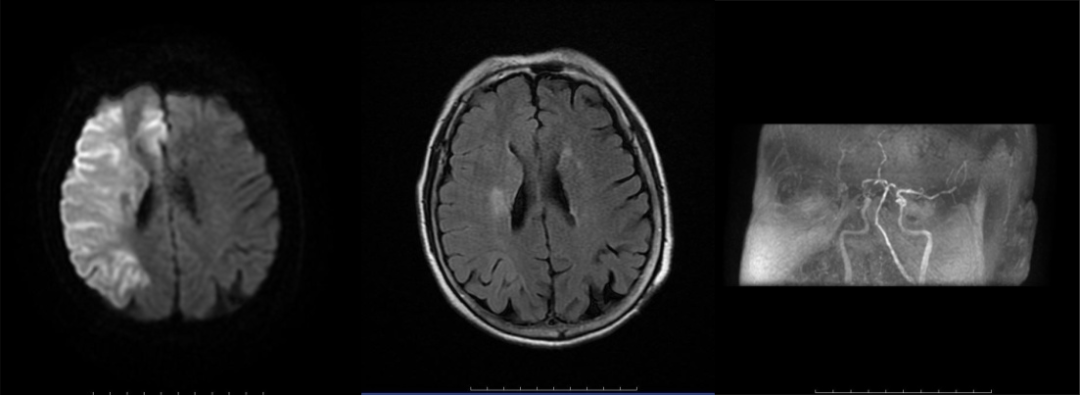

病历一:患者,71岁女性,因突发左侧肢体无力9小时,并伴有进行性意识障碍入院,经急诊MRI检查初步诊断为脑梗死。

神经内科介入团队接诊患者后迅速作出响应,实施造影,并采用Solitaire取栓支架及抽吸导管负压抽吸,成功取出条块状暗红色血栓。

右侧大脑中动脉起始部闭塞,右侧大脑中动脉开通,取出血栓。

经过紧急手术干预,患者的生命得到及时挽救。